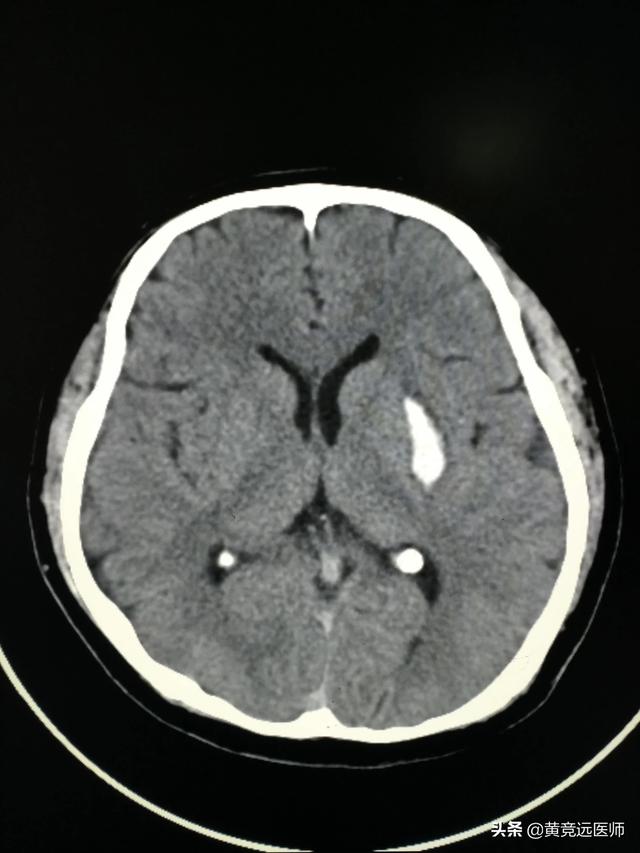

高血圧と診断されたら、血圧を安定した範囲に保ち、大きな変動を避けるために、生涯にわたって薬を服用する必要がある。薬を飲まなかったり、途中で服薬をやめたりすると、血圧のコントロールは容易ではなく、血圧が高すぎて脳の血管を破って頭蓋内出血を起こすと、後々QOL(生活の質)に重大な影響を及ぼすことになる。下の写真は高血圧性脳出血の患者で、片方の手足の動きに影響が出ることがある。したがって、健康は些細なことではなく、些細なことから始めるべきである!減塩、減塩の食事療法は、一度不幸にして撃たれても、あまり悲しまないで、普通の病院に行って、普通の医者を見つけて、薬を合理的に使うことが、健康の保証になる。